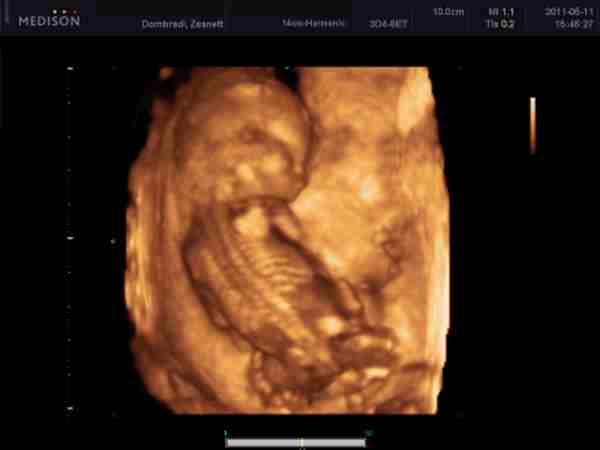

Amúgy a lányomról a 34. héten a Brendonban jó képek készültek, 44-et írt ki a pasi és kaptam dvd-t is, mind ilyen, úgyhogy megnyugtatásul - ráfér a feje, legalábbis az arcocskája ha nagyobb lesz, akkor is:

Kép

A pasi, már nem dolgozik náluk, annó az M5Brenyóban készültek a felvételek, és már megszünt az itteni babamozi :(